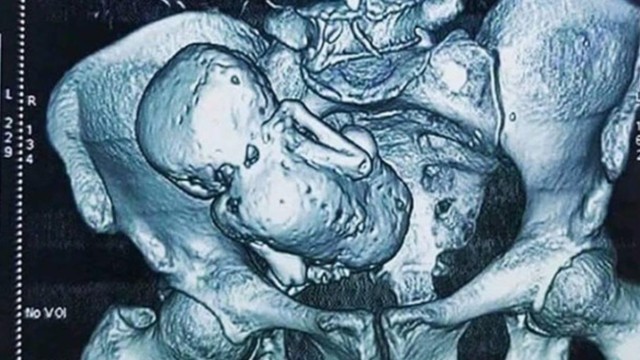

চিকিৎসা বিজ্ঞানে এক বিস্ময়কর ও বিরল ঘটনার সাক্ষী হয়েছেন চিকিৎসকেরা। ৭০ বছর বয়সী এক নারীর গর্ভ থেকে সফল অস্ত্রোপচারের মাধ্যমে উদ্ধার করা হয়েছে প্রায় ৪০ বছর ধরে জমে থাকা একটি ক্যালসিফায়েড ভ্রূণ, যা চিকিৎসা পরিভাষায় ‘লিথোপেডিয়ন’ বা পাথরের শিশু নামে পরিচিত।

পেটের তীব্র ব্যথা নিয়ে হাসপাতালে ভর্তি হলে প্রাথমিক পরীক্ষা ও স্ক্যানে নারীর উদরে একটি অস্বাভাবিক কঠিন ভর শনাক্ত হয়। পরবর্তী অস্ত্রোপচারে চিকিৎসকেরা নিশ্চিত হন, এটি বহু বছর আগে গর্ভে মারা যাওয়া একটি ভ্রূণ, যা দেহের ভেতরে ধীরে ধীরে পাথরের মতো শক্ত হয়ে গেছে।

চিকিৎসকদের মতে, লিথোপেডিয়ন অত্যন্ত বিরল একটি অবস্থা। সংক্রমণ থেকে শরীরকে রক্ষা করতে মৃত ভ্রূণ শোষিত না হয়ে ক্যালসিফায়েড হয়ে যায়। চিকিৎসা ইতিহাসে এমন ঘটনার সংখ্যা কয়েকশোর বেশি নয়।